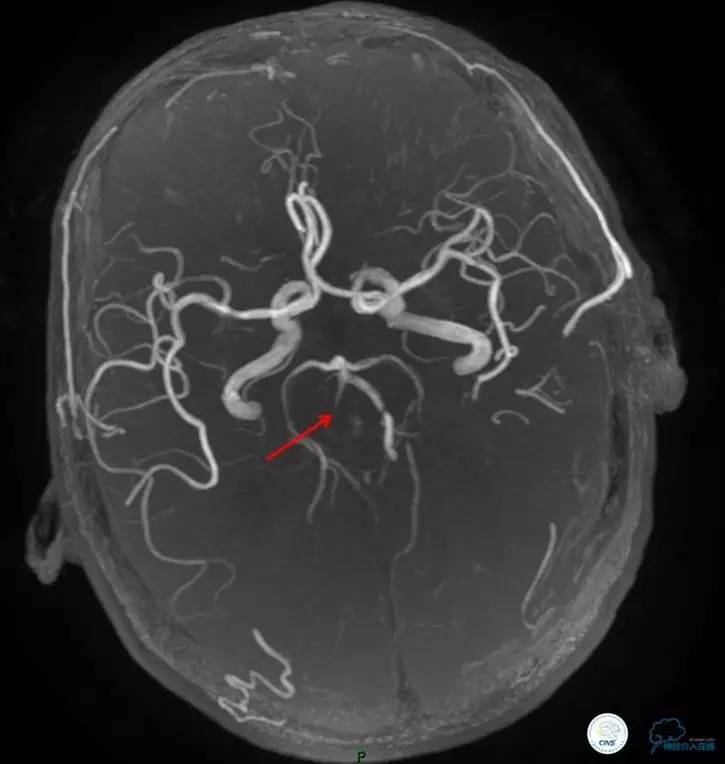

术前DSA

▼2013-12-13

术后仍残余部分狭窄,但头晕明显缓解。

术后3个月复查时予行支架内球囊扩张,狭窄改善。